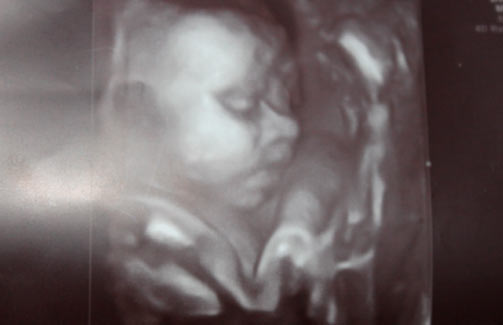

Photo échographie:

- Si vous devez subir une échographie imprévue, vous pouvez emmener votre mari ou votre enfant plus âgé avec vous. La vue sur l'écran du scanner sera sûrement inoubliable pour eux.